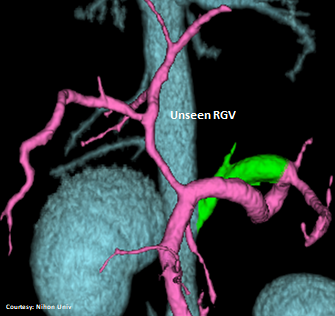

PRE-HEPATIC ENTRANCE

Does the RIGHT GASTRIC VEIN (RGV) contribute blood to the shunt?